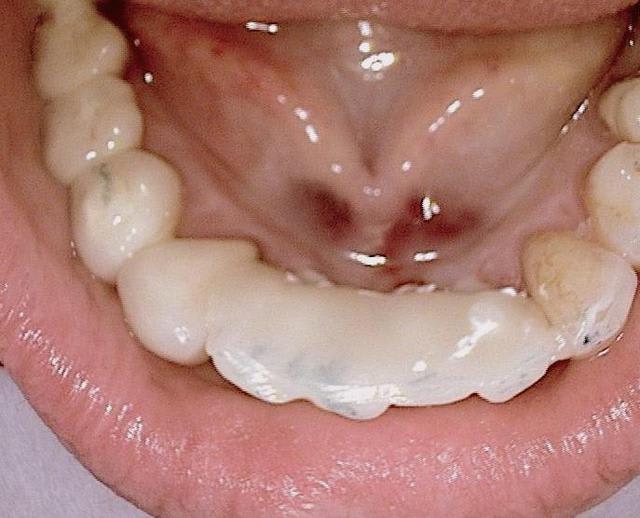

Oui tu as bien raison :-) Ci joint quelques photos en rapport avec ta question ....

20120327 154220 azpc5k - Eugenol

20120327 152704 psin9r - Eugenol

11 immidiat implantation ajhuew - Eugenol